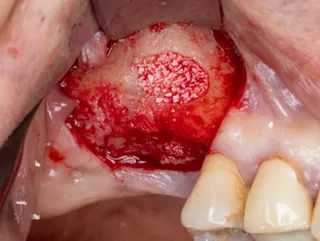

7. Sinus mucosa detached.

8. Verification of the absence of mucosal adherence at the Beta angle and at the inter-sinus-nasal septum using a Freer sinus elevator.